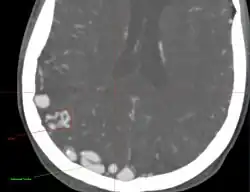

• Originally described by Luschka and Virchow in the mid 1800s, AVMs are abnormal communications between arteries and veins without the normal capillary flow.

• Abnormal communication between artery and vein, with disproportionate and unbalanced hydrodynamic stress across them. The direct connection between the arterial and venous systems exposes the venous system to abnormally high pressures and results in the formation of enlarged feeding vessels and enlarged draining venous structures.

• Point of abnormal communication is known as the nidus